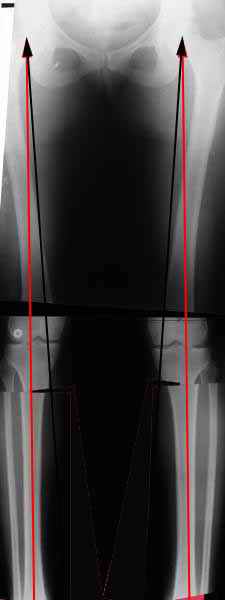

AVM> Александр, а не могли бы вы представить ваши схемы расчета? С учетом

Вот, с учетом и без учета, и на разных уровнях...

Саша Артемьев, может, для данного случая свой вариант нарисуешь?

Из приведнной схемы не совсеим понял что означают разноцветные линии.

И зачем латерализация периферического фрагмента. Я всегда делаю медиализацию. См схему. И для данного случая медиализация подходит как нельзя лучше.

a> Из приведнной схемы не совсеим понял что означают разноцветные линии.

Черные - это нынешняя механическая ось. Красные - это планируемая правильная ось.

a> И зачем латерализация периферического фрагмента.

;-) Читайте Палея. Стр. 114-115.

a> Я всегда делаю медиализацию. См схему. И для данного случая

Медиализация - это чисто эстетический прием, как я понимаю. Поскольку если делать остеотомию ниже вершины деформации, для восстановления оси надо делать смещение по ширине, в данном случае как раз латерализацию.

А вот на схемке без осей - там на разных уровнях (который правильнее?) устранение варуса чисто открытым клином без медиализации-латерализации. Если как-то так сделать - этого недостаточно будет?